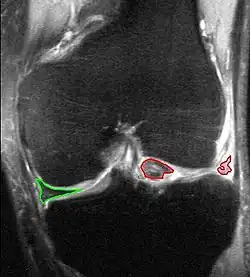

X-ray images (normally during weightbearing) can be obtained to rule out other conditions or to see if the patient also has osteoarthritis. The menisci themselves cannot be visualised with plain radiographs. If the diagnosis is not clear from the history and examination, the menisci can be imaged with magnetic resonance imaging (an MRI scan). This technique has replaced previous arthrography, which involved injecting contrast medium into the joint space. In straightforward cases, knee arthroscopy allows quick diagnosis and simultaneous treatment. Recent clinical data shows that MRI and clinical testing are comparable in sensitivity and specificity when looking for a meniscal tear.